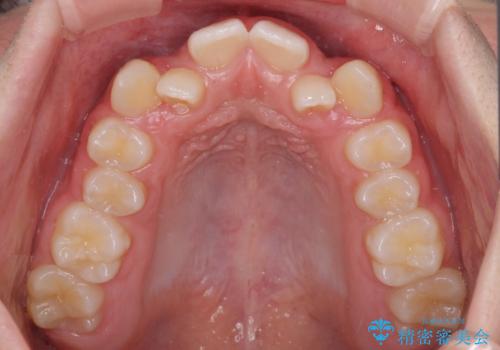

中学生のワイヤー矯正 クロスバイトを短期間で改善

- 前歯のクロスバイトを気にして来院された患者様です。

叢生のため磨き残しの多い歯列でしたが、1年弱で治療を終了でき、磨き残しや歯肉の腫れが著しく改善されました。